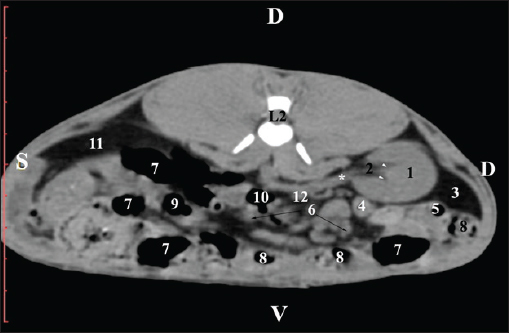

At the L3 level, the anatomical adjacencies of the right kidney with the pars descendens of the duodenum, ileum, cecum, and colon descendens were visualized. Hypoattenuated right ureter and normoattenuated gl. adrenalis dextra were situated medially to the right kidney. Extremitas caudalis of the right kidney was a clearly visible normoattenuated finding, surrounded by hypoattenuated borders of abdominal adipose collections (Figs. 6 and 7).

Fig. 6. Pre-contrast CT anatomical scan of the regio-abdominis media at the cranial L3 edge level. (1) Ren dexter; (2) lobus caudatus (proc. caudatus) with visceral adipose tissue; (3) gl. adrenalis dextra; (4) pars descendens of the duodenum; (5) ileum; (6) cecum; (7) colon ascendens; (8) jejunum; (9) lien; (10) colon ascendens; (11) colon transversum; (12) colon descendens, (*) mesenterium.

Fig. 7. Pre-contrast computed tomography (CT) anatomical scan of the regio-abdominis media at the caudal L3 edge level. (1) Ren dexter; (2) adipose collection; (3) cecum; (4) colon ascendens; (5) colon transversum; (6) colon descendens; (7) mesenterium.

The transverse pre-contrast examination of the regio abdominis media at the L3 level (through the cranial part of the vertebra) revealed the left kidney’s extremitas cranialis as an oval soft tissue with normoattenuated soft tissue characteristics. Ventrally, the kidney was adjacent to the duodenal pars ascendens, ileum, colon ascendens, and colon descendens. Hypoattenuated abdominal adipose collections were observed around it (Figs. 8 and 9).

Fig. 8. Pre-contrast computed tomography (CT) anatomical scan of the regio-abdominis media at the cranial L3 edge level. (1) Ren sinister; (2) adipose collections; (3) cecum; (4) colon ascendens; (5) jejunum; (6) pars ascendens of the duodenum; (7) colon descendens; (8) colon transversum; (9) colon descendens.

Fig. 9. Pre-contrast computed tomography (CT) anatomical scan of the regio-abdominis media at the caudal L3 edge level. (1) Ren dexter; (2) adipose collections; (3) cecum; (4) colon ascendens; (5) jejunum; (6) pars ascendens of the duodenum; (7) colon descendens.